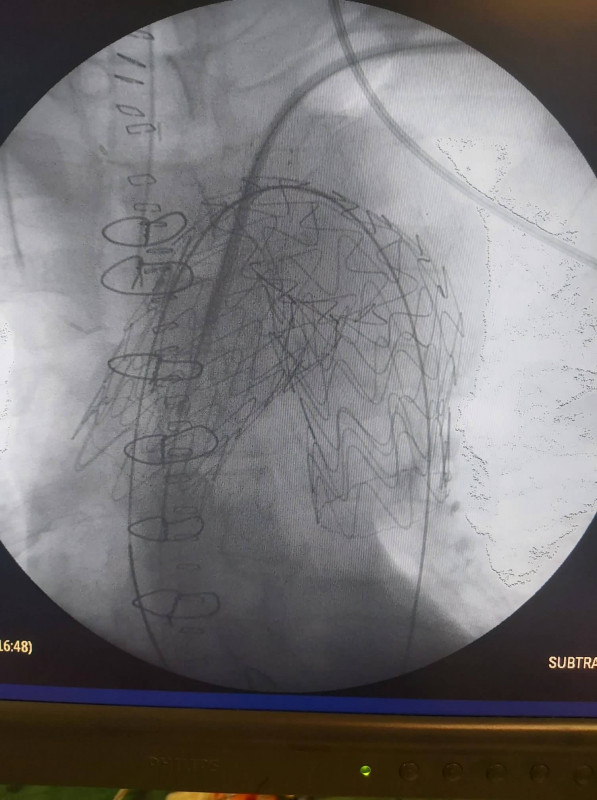

Στο Πανεπιστημιακό Γενικό Νοσοκομείο Ιωαννίνων άρχισε να εφαρμόζεται πλέον η νέα πρωτοποριακή μέθοδος της υβριδικής χειρουργικής αντιμετώπισης των διαχωριστικών ανευρυσμάτων του αορτικού τόξου, τα οποία είναι πολύ επικίνδυνα για τη ζωή των ασθενών.

Η υπεροχή του νέου τρόπου χειρουργικής αντιμετώπισης αυτής της επικίνδυνης κατάστασης, που πραγματοποιείται σε δύο στάδια, οφείλεται στο γεγονός ότι, πραγματοποιείται χωρίς τη χρήση εξωσωματικής κυκλοφορίας με υποθερμία και χωρίς διακοπή της καρδιακής και εγκεφαλικής λειτουργίας, με αποτέλεσμα οι ασθενείς να αναρρώνουν γρήγορα και με ελάχιστες πιθανότητες επιπλοκών εμφράγματος, εγκεφαλικού, παραπληγίας, αιμορραγίας, λοιμώξεων και θανάτου.